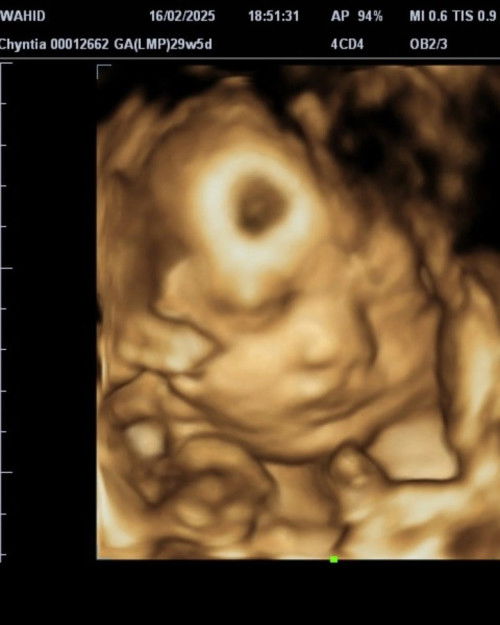

aku mau lahir normal tapi dokterku bilang bayinya lebih besar dari hitungan bulan jadi sulit untuk lahir normal apa ada saran bund biar bisa lahir normal aku hamil 29week 5 day bbj 1613